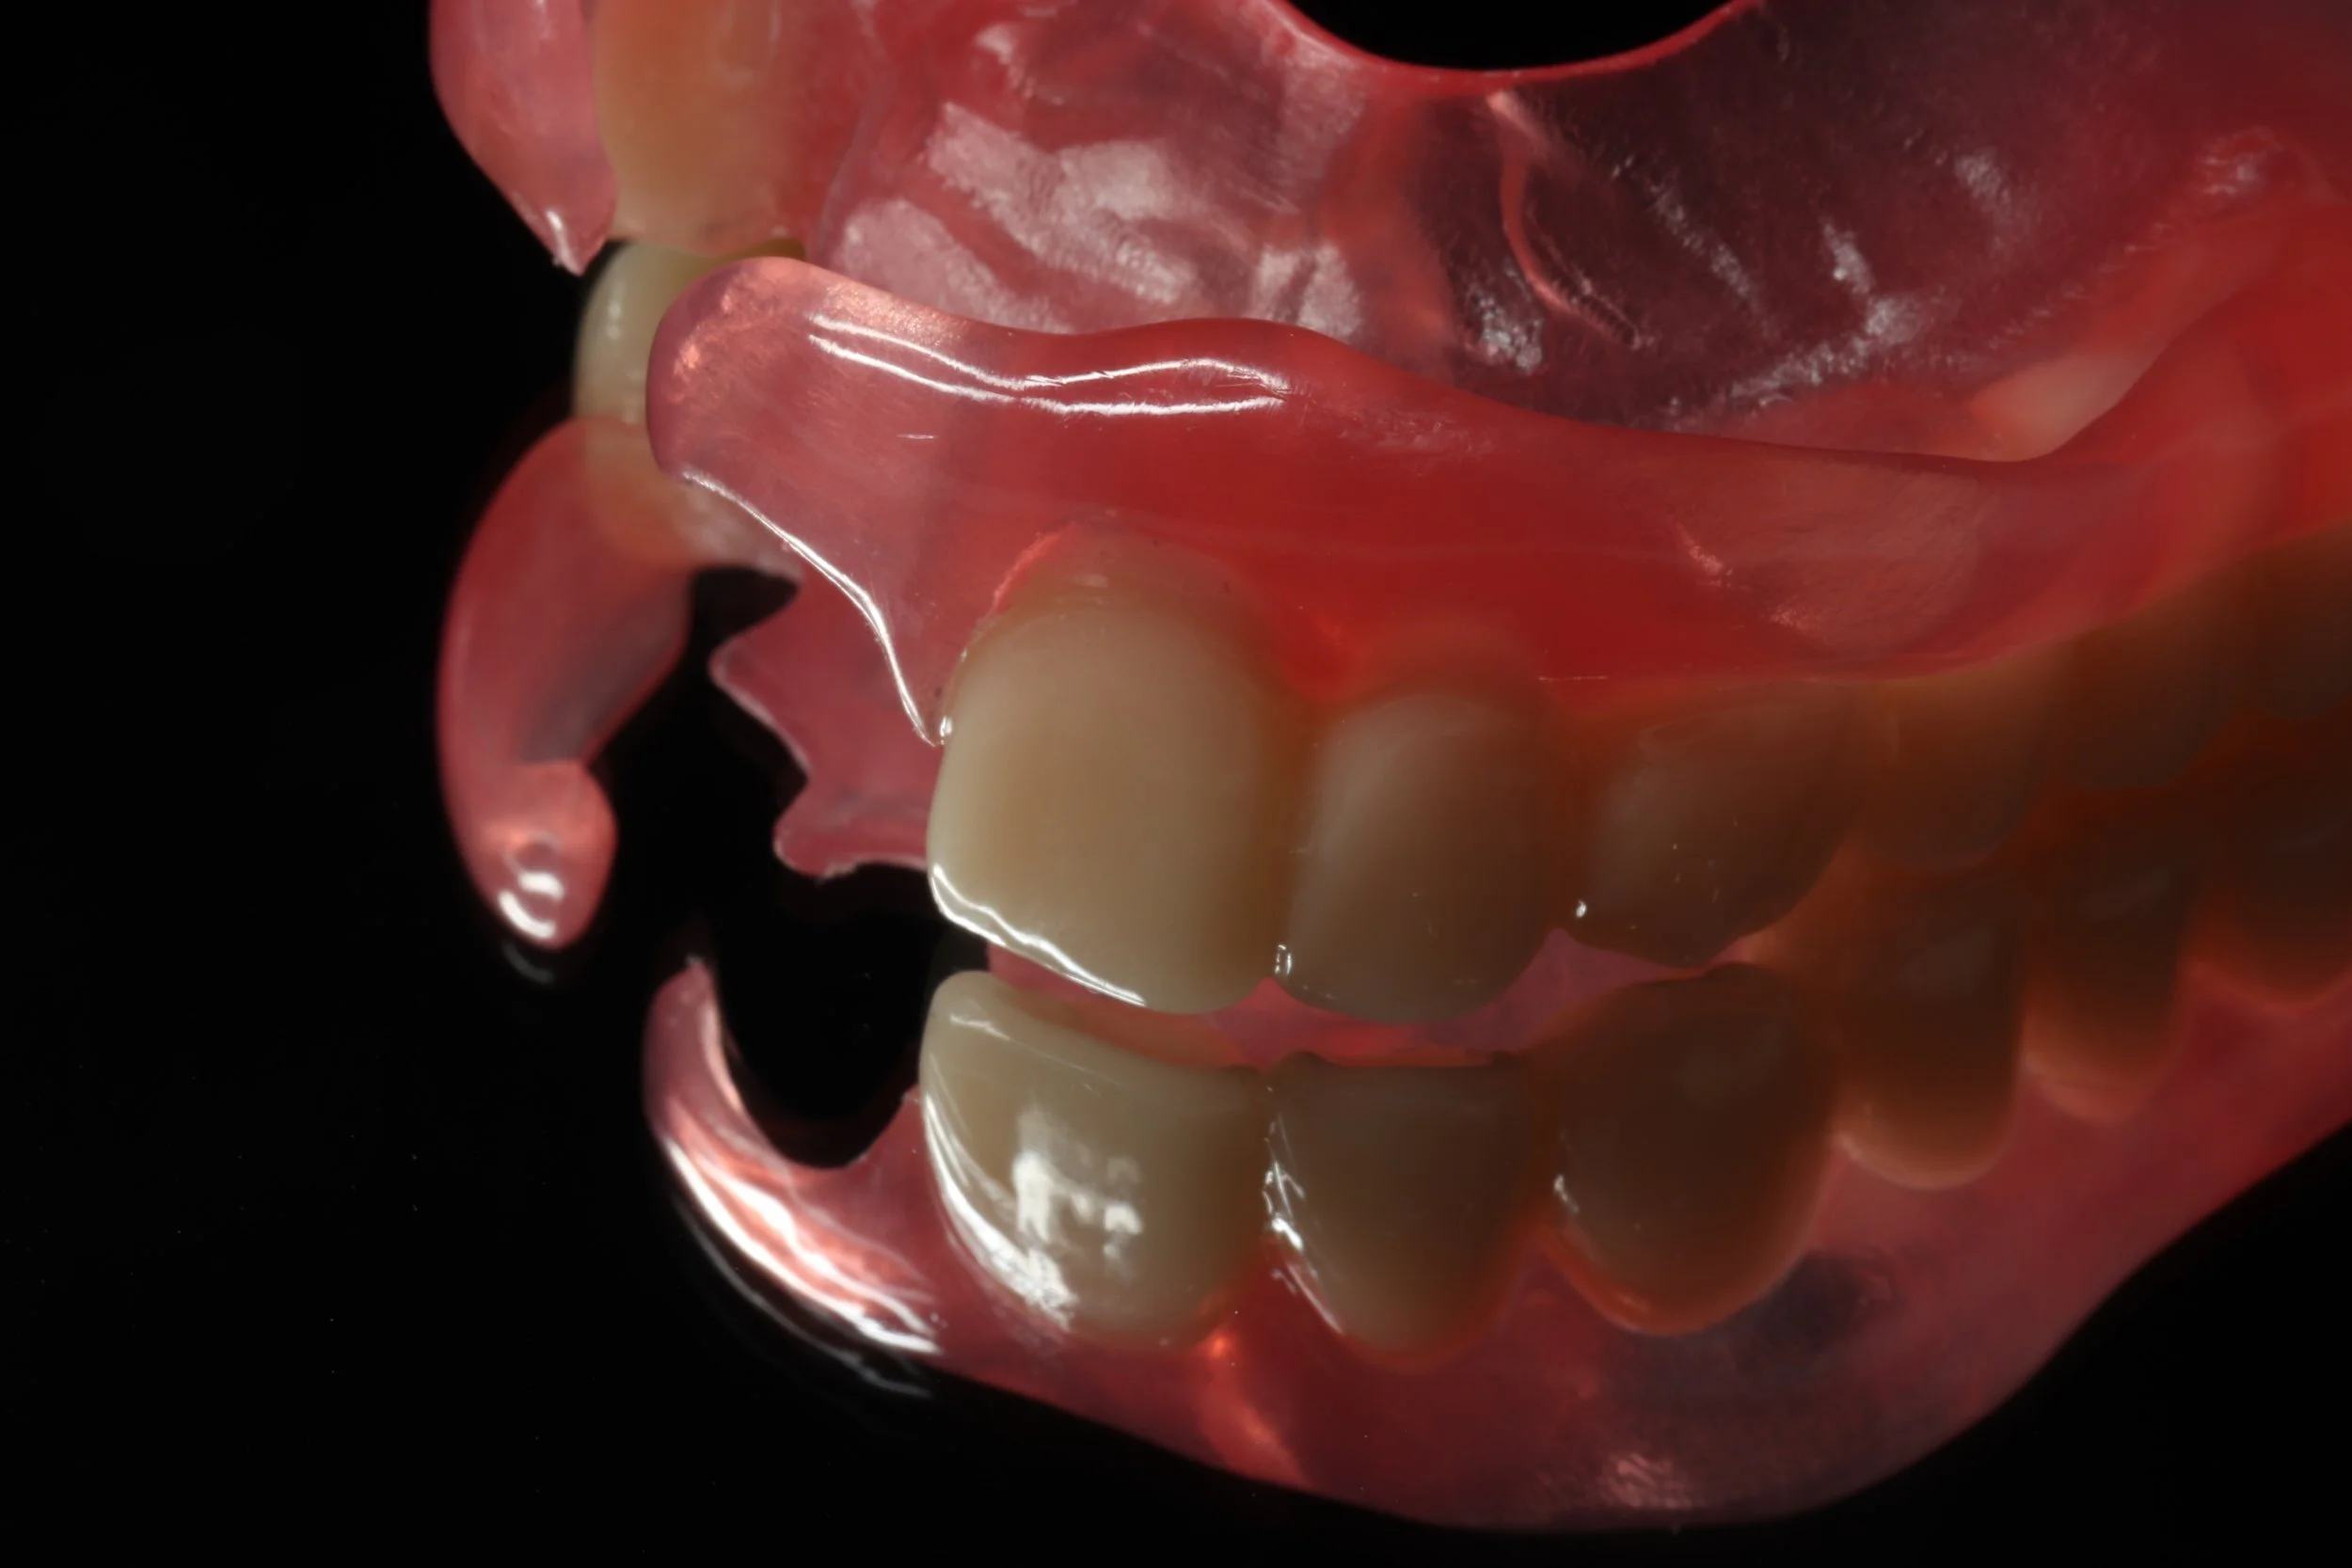

今回はできるだけ薄く作りたいという希望もあったことから、金属床を用い製作、前歯の抜歯とともに同日に新しい入れ歯を装着。

デジタルデンチャー

奥の歯には、金属で入れ歯を止めるバネを製作し、前歯の見える部分には、透明なレジンクラスプを使用しました。